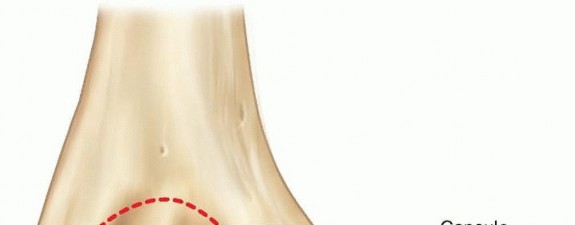

Chapter 6 Open Reduction and Internal Fixation of Fractures of the Medial Epicondyle Brian G. Smith Kristan A…